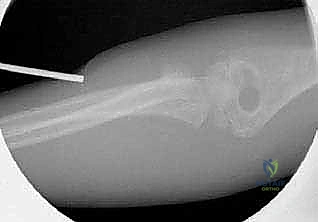

1. الرد المغلق والتثبيت عبر الجلد (CRPP - Closed Reduction and Percutaneous Pinning)

هذه هي التقنية السائدة والمفضلة عالمياً لعلاج كسور عنق الكعبرة لدى الأطفال (تقنية ميتازو Métaizeau Technique). وهي تقنية طفيفة التوغل لا تتطلب شقاً جراحياً كبيراً، مما يحافظ على الأنسجة المحيطة ويقلل من خطر الندبات وتيبس المفصل.

بما أن كسور عنق الكعبرة